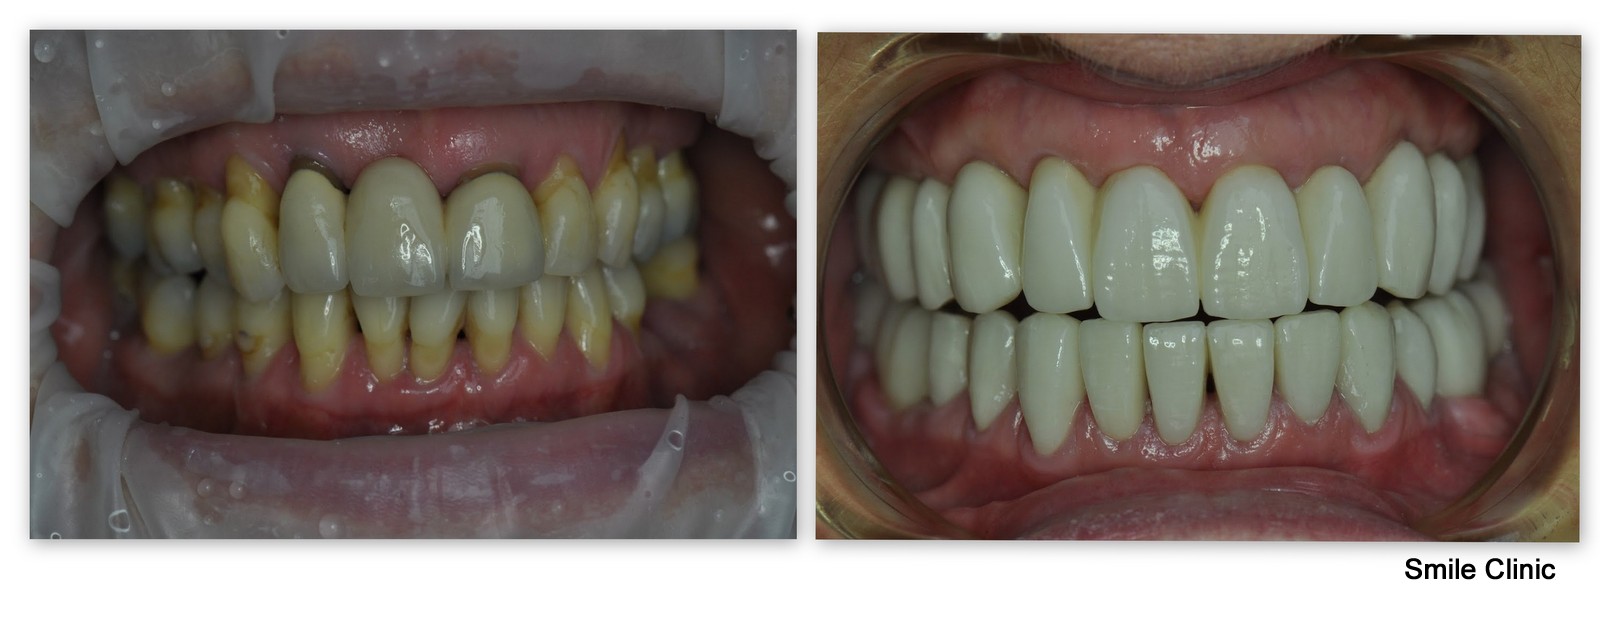

Pamela’s smile before the treatment and after the treatment

On her final visit, we fitted the final implant crowns and 9 zirconium crowns. Pamela left our clinic with a wide smile, and she left us this pleasant testimonial: